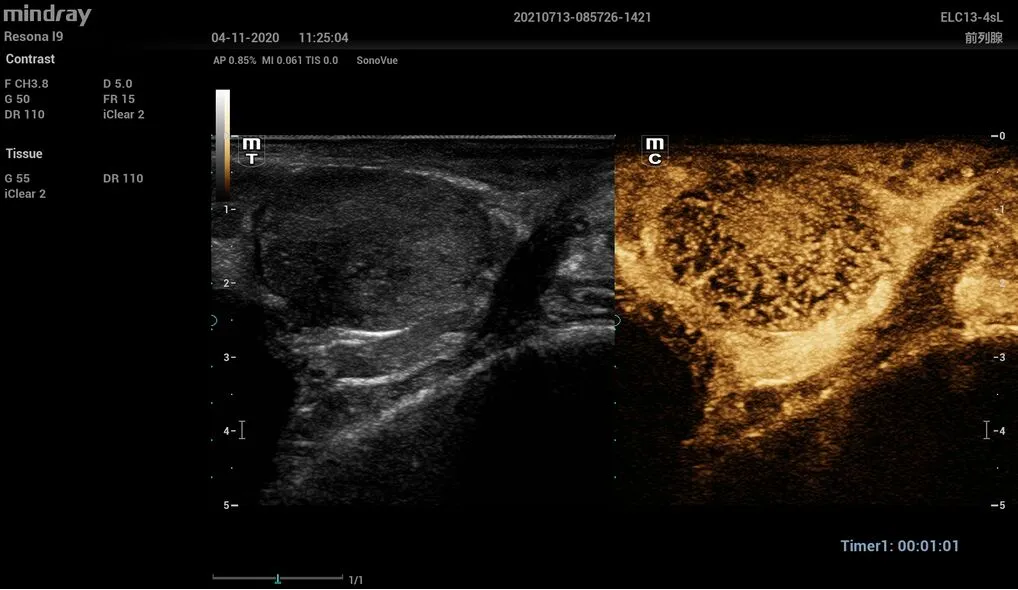

- UWN+ (диагностика очаговых поражений с помощью контрастов)

Диагностика очаговых поражений с помощью контрастов UWN+

Особенностью Resona I9 является высокая чувствительность функции UWN+ к низкоамплитудным сигналам и бо́льшее время персистенции контрастного вещества. Метод может использовать как нелинейные фундаментальные сигналы, так и вторую гармонику.

- ELC13-4s – биплановый датчик для исследований в урологии.

Предстательная железа, ELC3-4sL